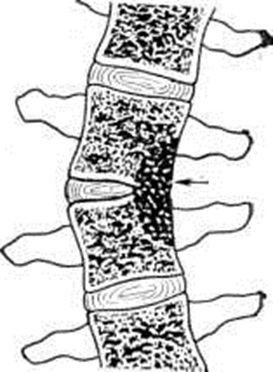

Деструкция тел позвонков сопровождается их клиновидной деформацией — это ведёт к углообразному кифотическому искривлению позвоночника (смотри полный свод знаний: Кифоз) в виде горба (gibbus), что является самым характерным признаком Спондилит У детей кифоз появляется раньше и прогрессирует быстрее, чем у взрослых. Наибольшей степени кифотическая деформация достигает при локализации процесса в грудном отделе позвоночника. С появлением кифоза постепенно деформируется вся грудная клетка, смещаются и сдавливаются находящиеся в ней сосуды и органы, развивается легочно-сердечная недостаточность и другие нарушения. При боковой деструкции тел позвонков развивается сколиотическая деформация (смотри полный свод знаний: Сколиоз), более характерная для поясничного отдела позвоночника (рисунок 3). Чаще имеют место сочетанные деформации. Межпозвоночные диски вследствие нарушения трофики постепенно уменьшаются в размерах и истончаются. Тела позвонков, разрушаясь, сближаются, соприкасаются и при длительно существующем процессе образуют нередко единый конгломерат, блок тел позвонков, включающий очаги деструкции, остатки разволокнённых дисков. Задние отделы позвоночника также сливаются воедино в виде панциря, закрывающего спинной мозг.

При центральном расположении первичного очага И. Л. Тагер и В. А. Дьяченко выделяют четыре фазы развития туберкулёзного Спондилит В первой фазе образуется изолированная костная каверна, обнаружение которой возможно лишь при появлении зоны склеротического уплотнения вокруг очага деструкции. Во второй фазе отмечается прорыв содержимого каверны. Обычно происходит внутридисковый прорыв с разрушением межпозвоночного диска, значительно реже — внедисковый, в сторону позвоночного канала. Наряду с деструкцией костной ткани в этой фазе определяется сужение межпозвоночной щели. В третьей фазе происходит контактное разрушение соседнего позвонка, разрушение межпозвоночного диска и формирование натечного абсцесса. В четвертой фазе выявляется далеко зашедшая деструкция в виде разрушения нескольких рядом расположенных позвонков, сближения оставшихся их отделов с образованием блока тел позвонков и уплотнением тени абсцесса.

По мере затихания и последующей стабилизации туберкулёзного процесса натечный абсцесс может рассосаться или обызвествиться. Обызвествленные участки имеют вид мелких или крупных конгломератов (рисунок 6). Рентгенологические признаками затихания туберкулёзного Спондилит являются: уменьшение размеров абсцесса, увеличение его плотности или обызвествление; стабильность рентгенологическое признаков без появления новых деструктивных изменений, четкая отграниченность каверн; окостенение фиброзных колец и продольных связок позвоночника в виде скобок и краевых разрастаний; костное спаяние (анкилозирование) дуг и суставных отростков позвонков.